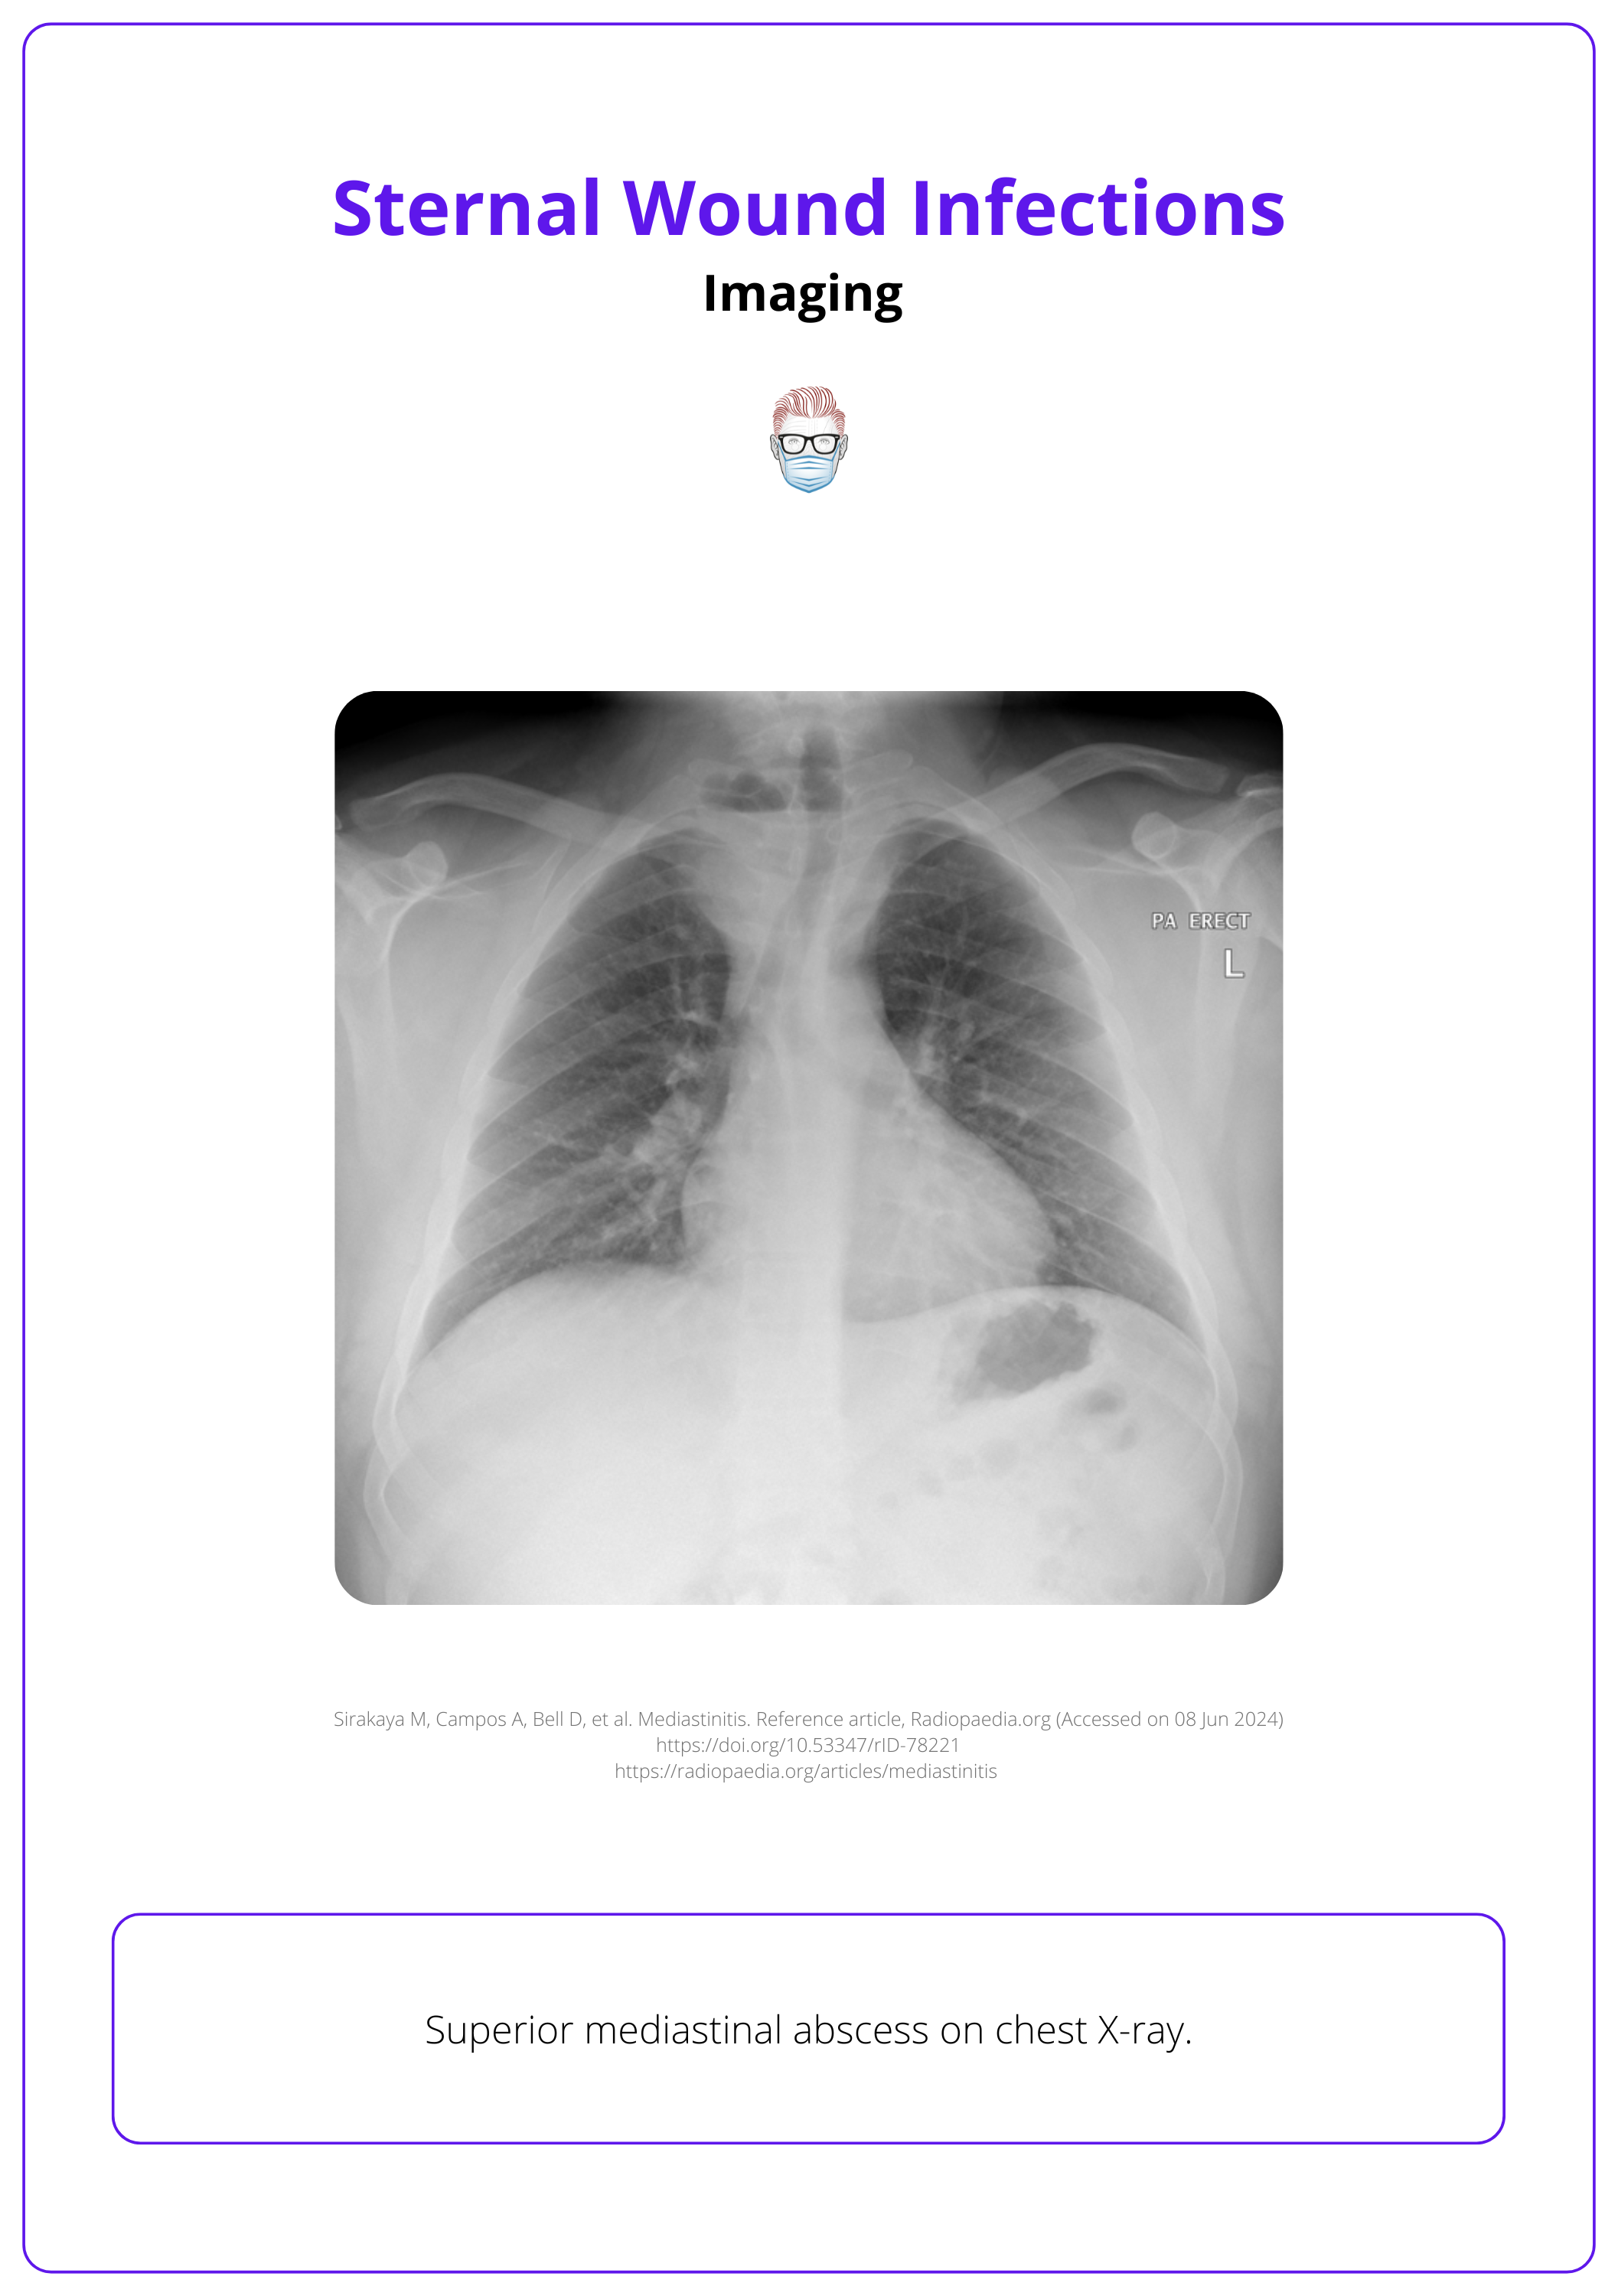

Diagnosis is clinical and can be supported by laboratory tests such as FBC, ESR, CRP, and blood culture and imaging such as CXR and CT.